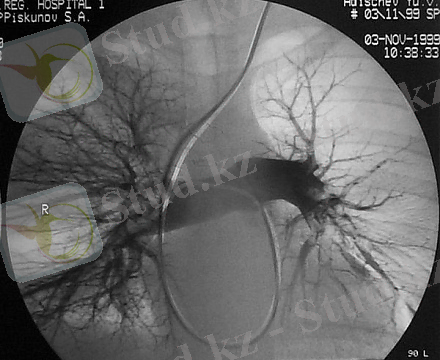

- өкпе сцинтиграфиясы (Өкпенің ұлпасындағы қан айналымын бұзу өкпе тіндерінің эмболиясына байланысты қан ағысының төмендеуі немесе болмауы туралы көрсетеді)

- ангиопульмонография (қан ұйығышының орналасуын және өлшемін дәл анықтау үшін)